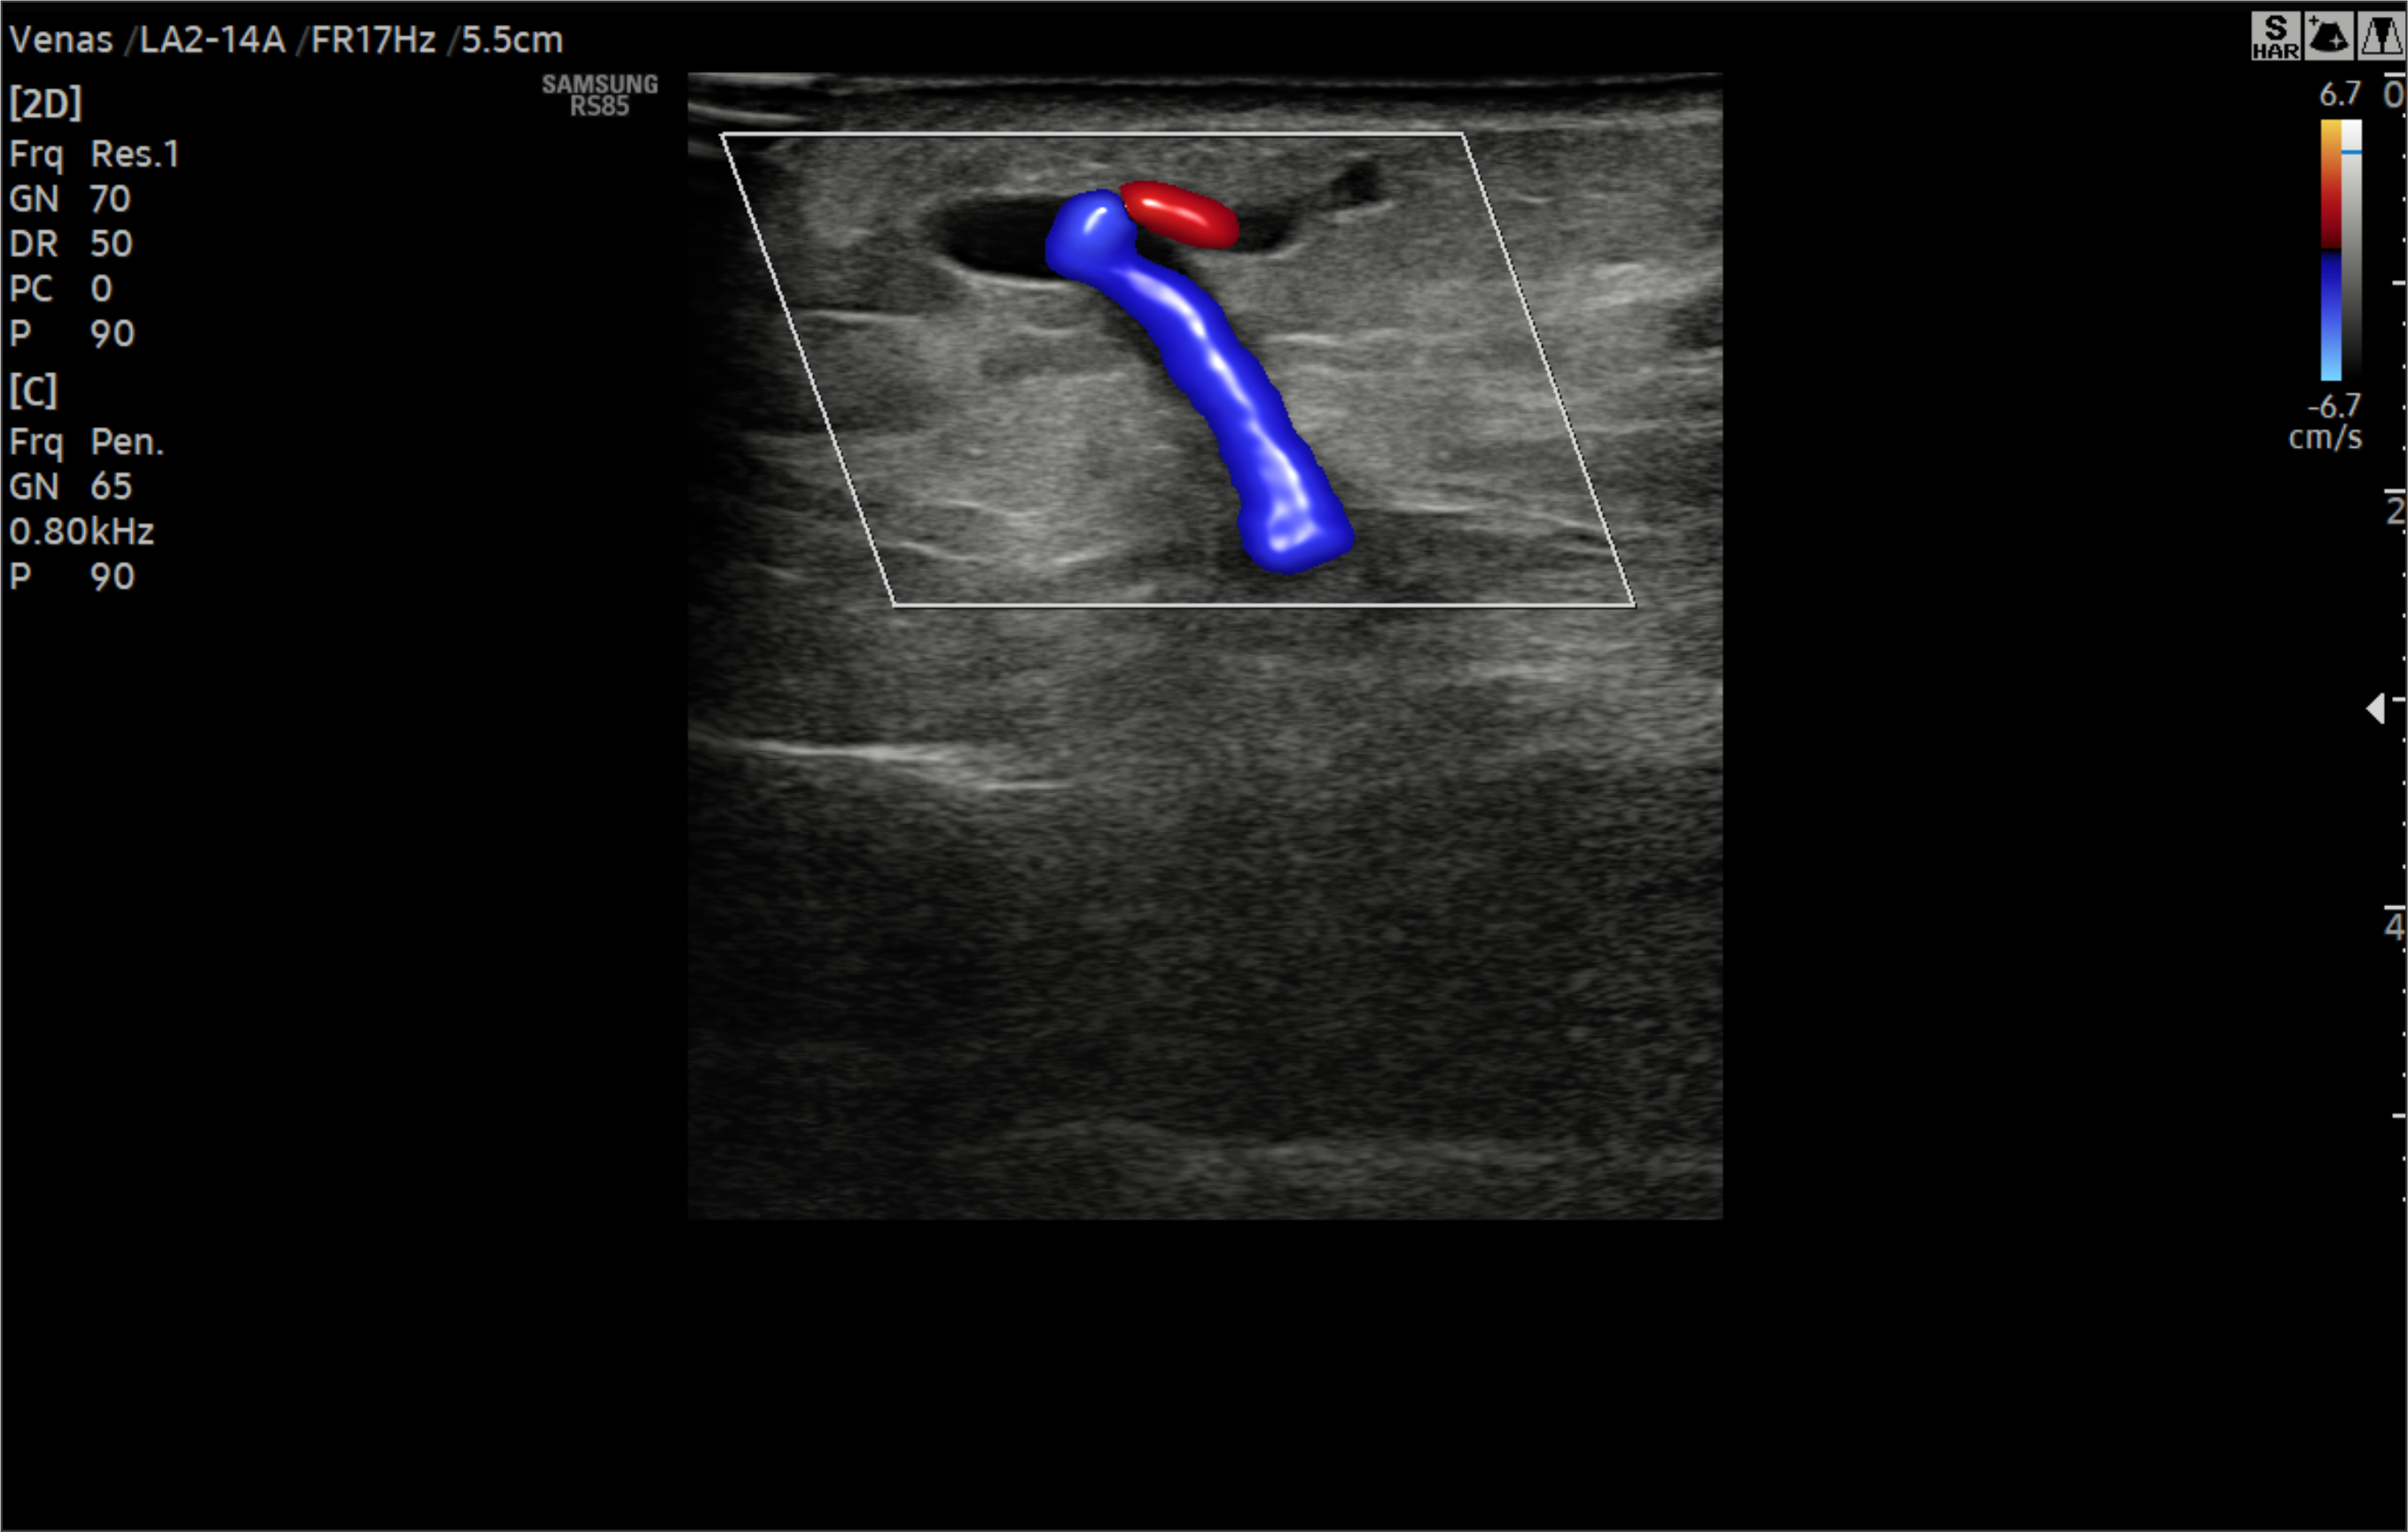

En Diagnoimagen incorporamos un enfoque de ecografía multiparamétrica, combinando modo B, Doppler color, Doppler de microflujo y elastografía, lo que nos permite una evaluación más completa y precisa en múltiples patologías.

🔹La ecografía Doppler permite evaluar el flujo sanguíneo en arterias y venas, siendo fundamental para el diagnóstico de insuficiencia venosa, várices, trombosis, estenosis carotídea y patología hepática.